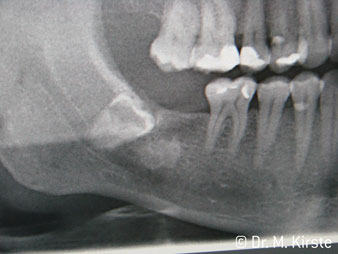

Le contre-angle avec tête angulée à 45° a surtout été choisi pour ses nombreux avantages. Les collègues qui exercent en chirurgie, et à qui cet instrument est principalement destiné, apprécieront très vite la possibilité de travailler efficacement dans des zones très étroites. En particulier, lors d’extractions de dent de sagesse (Ill. 2), où il n'y a pas besoin d’un grand angle d’écartement des tissus mous dans la région de la joue (Ill. 3). Pendant la préparation, une légère rotation de la tête de l’instrument permet un travail rapide et sans risque dans la zone rétromolaire.

La conception particulière des roulements à l'intérieur de la tête du contre-angle garantit un fonctionnement silencieux de l’instrument rotatif et lui procure une grande efficacité de coupe, sans à-coup ; ce qui est appréciable lors des interventions chirurgicales comme par exemple les séparations dentaires et résections apicales (Ill. 4-9).